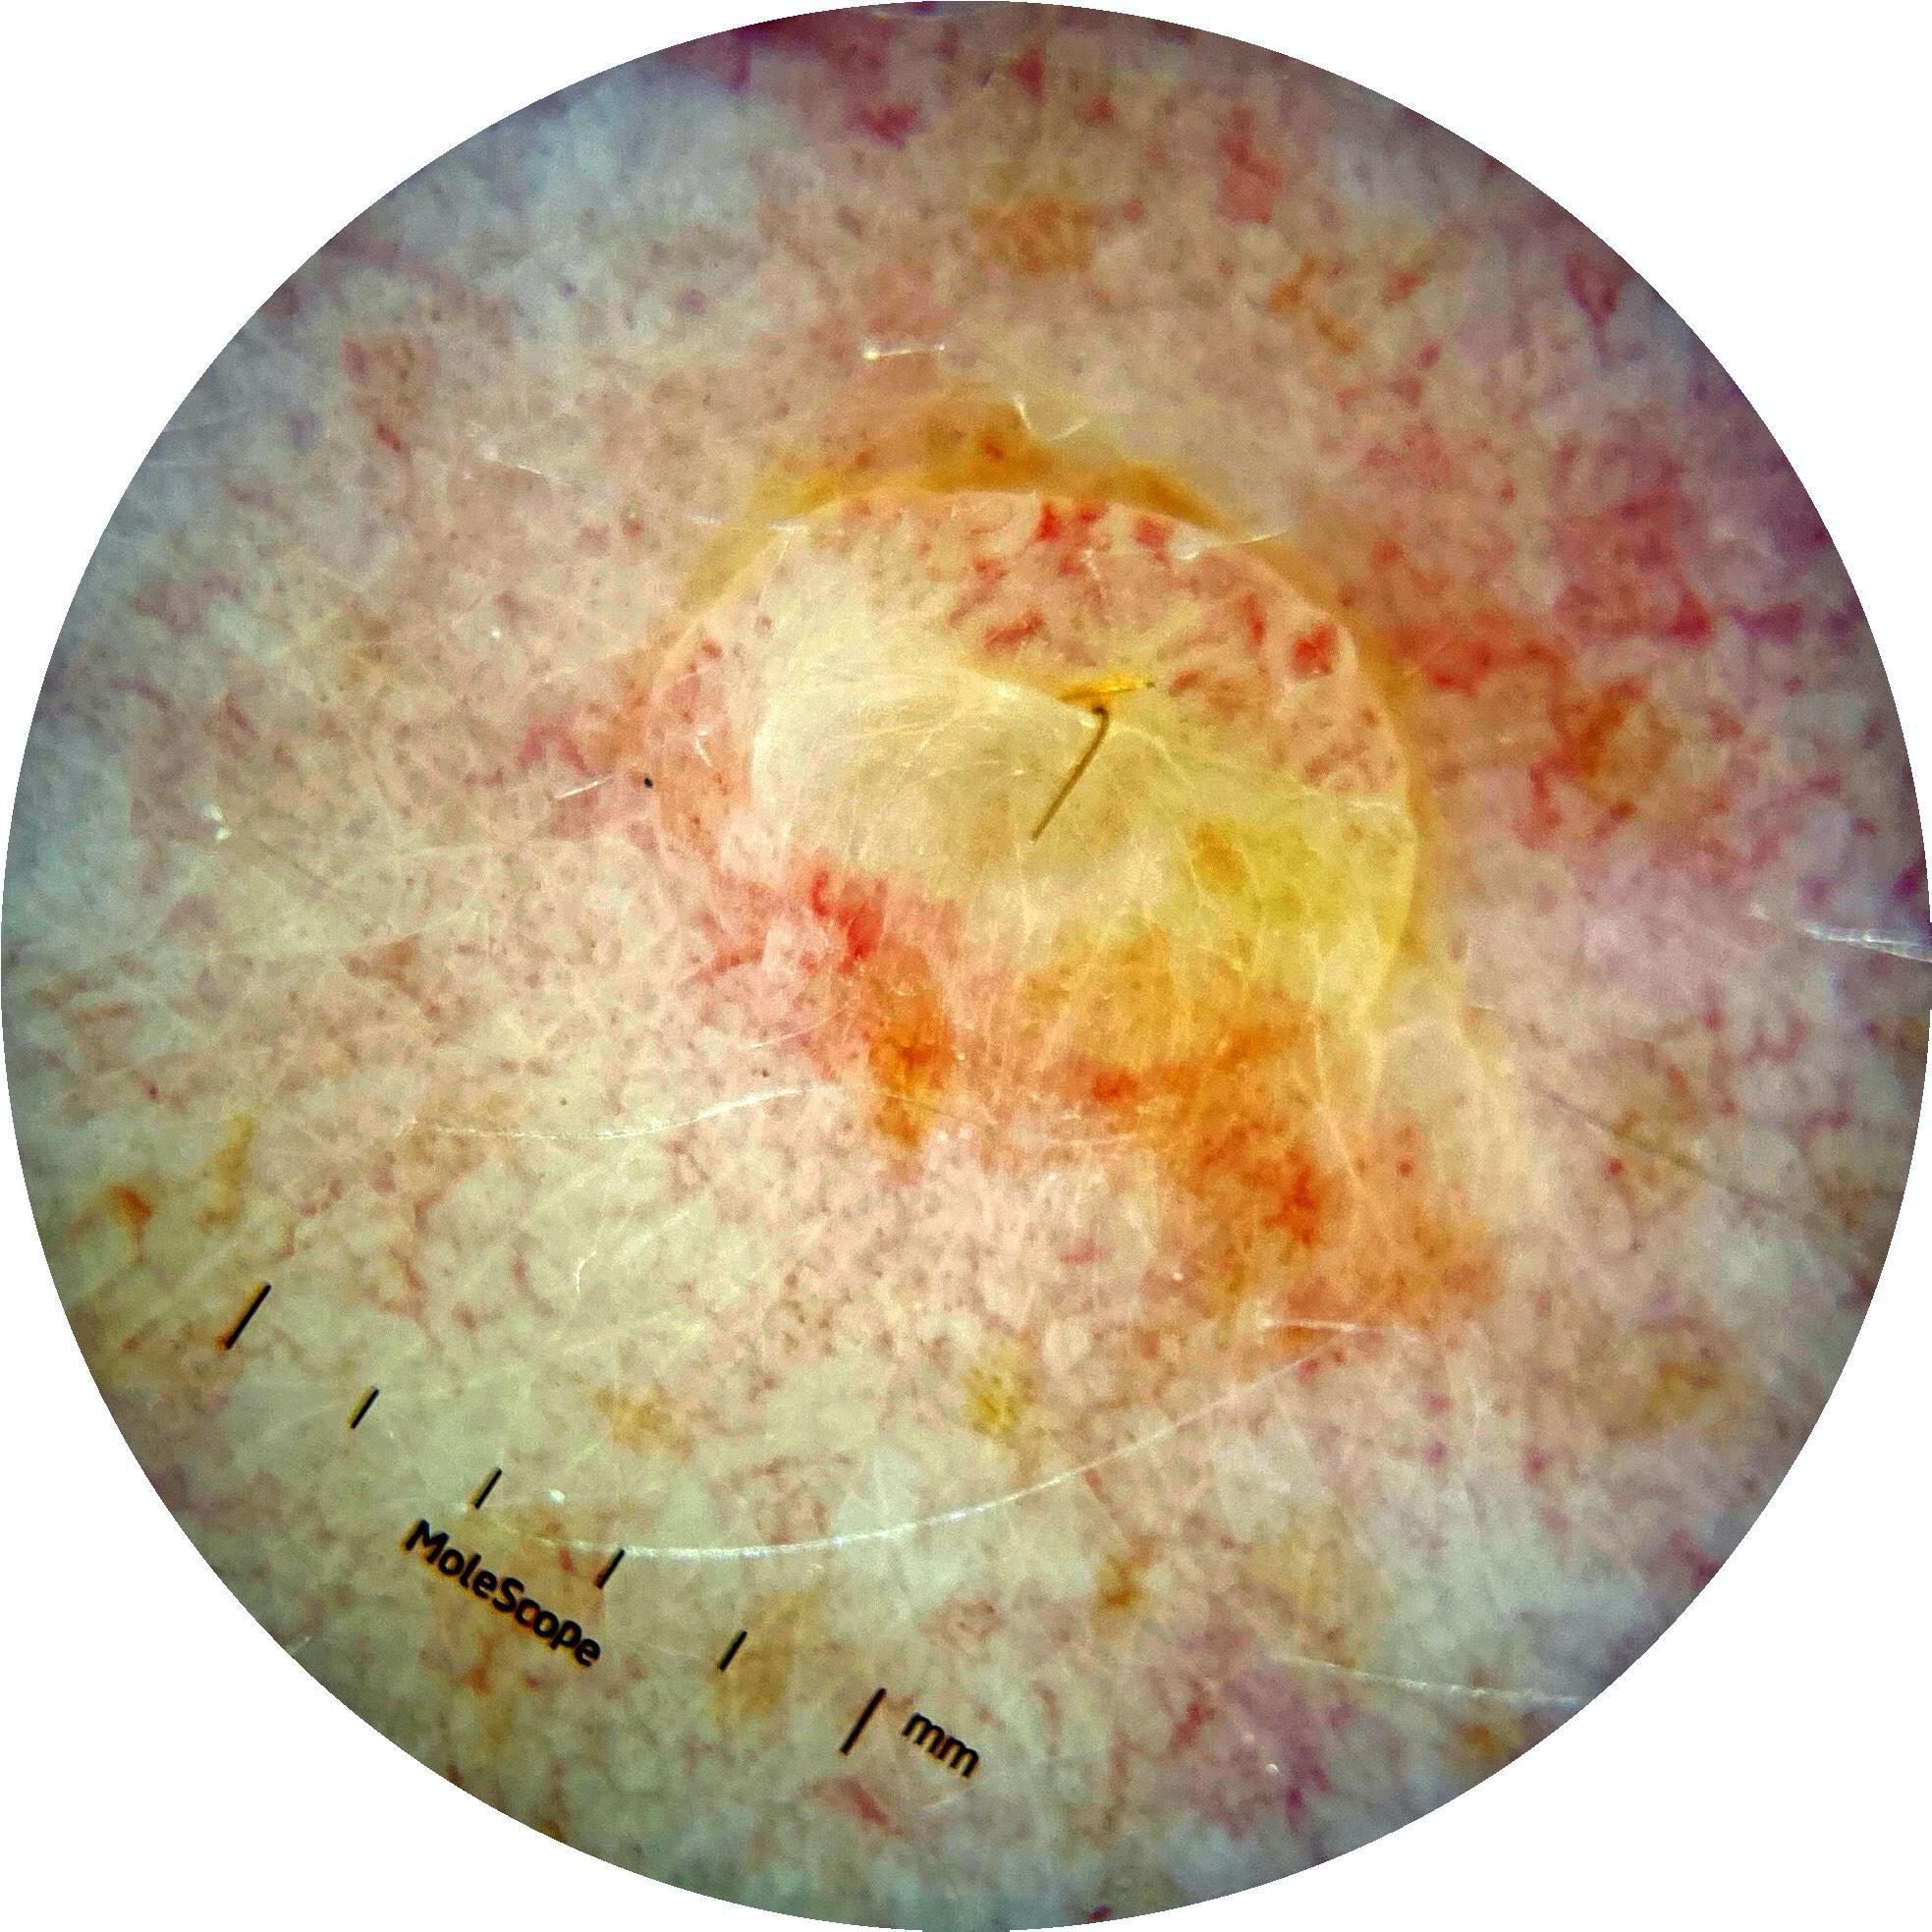

ISIC_7193897

MEL-SELF Trial, https://www.sydney.edu.au/medicine-health/our-research/research-centres/melself-project.html

IP_3751325

IL_3780211

Field Value

acquisition_day 251

age_approx 65

anatom_site_1 Lower extremity

anatom_site_general lower extremity

diagnosis_1 Benign

diagnosis_confirm_type single image expert consensus

image_type dermoscopic

lesion_id IL_3780211

patient_id IP_3751325

personal_hx_mm True

sex female